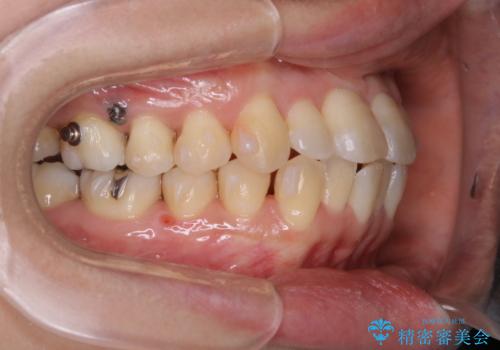

矯正用アンカースクリューを埋入し、上下左右の歯を後ろに動かすことで歯を並べるスペースを作りました。

元々内側に倒れていた右下の奥歯は、ゴムかけを追加で行っていただくことによりしっかり起こすことが出来ました。

歯並びが綺麗になったことでモチベーションが上がり、銀歯からセラミックへのやり替えも行っております。